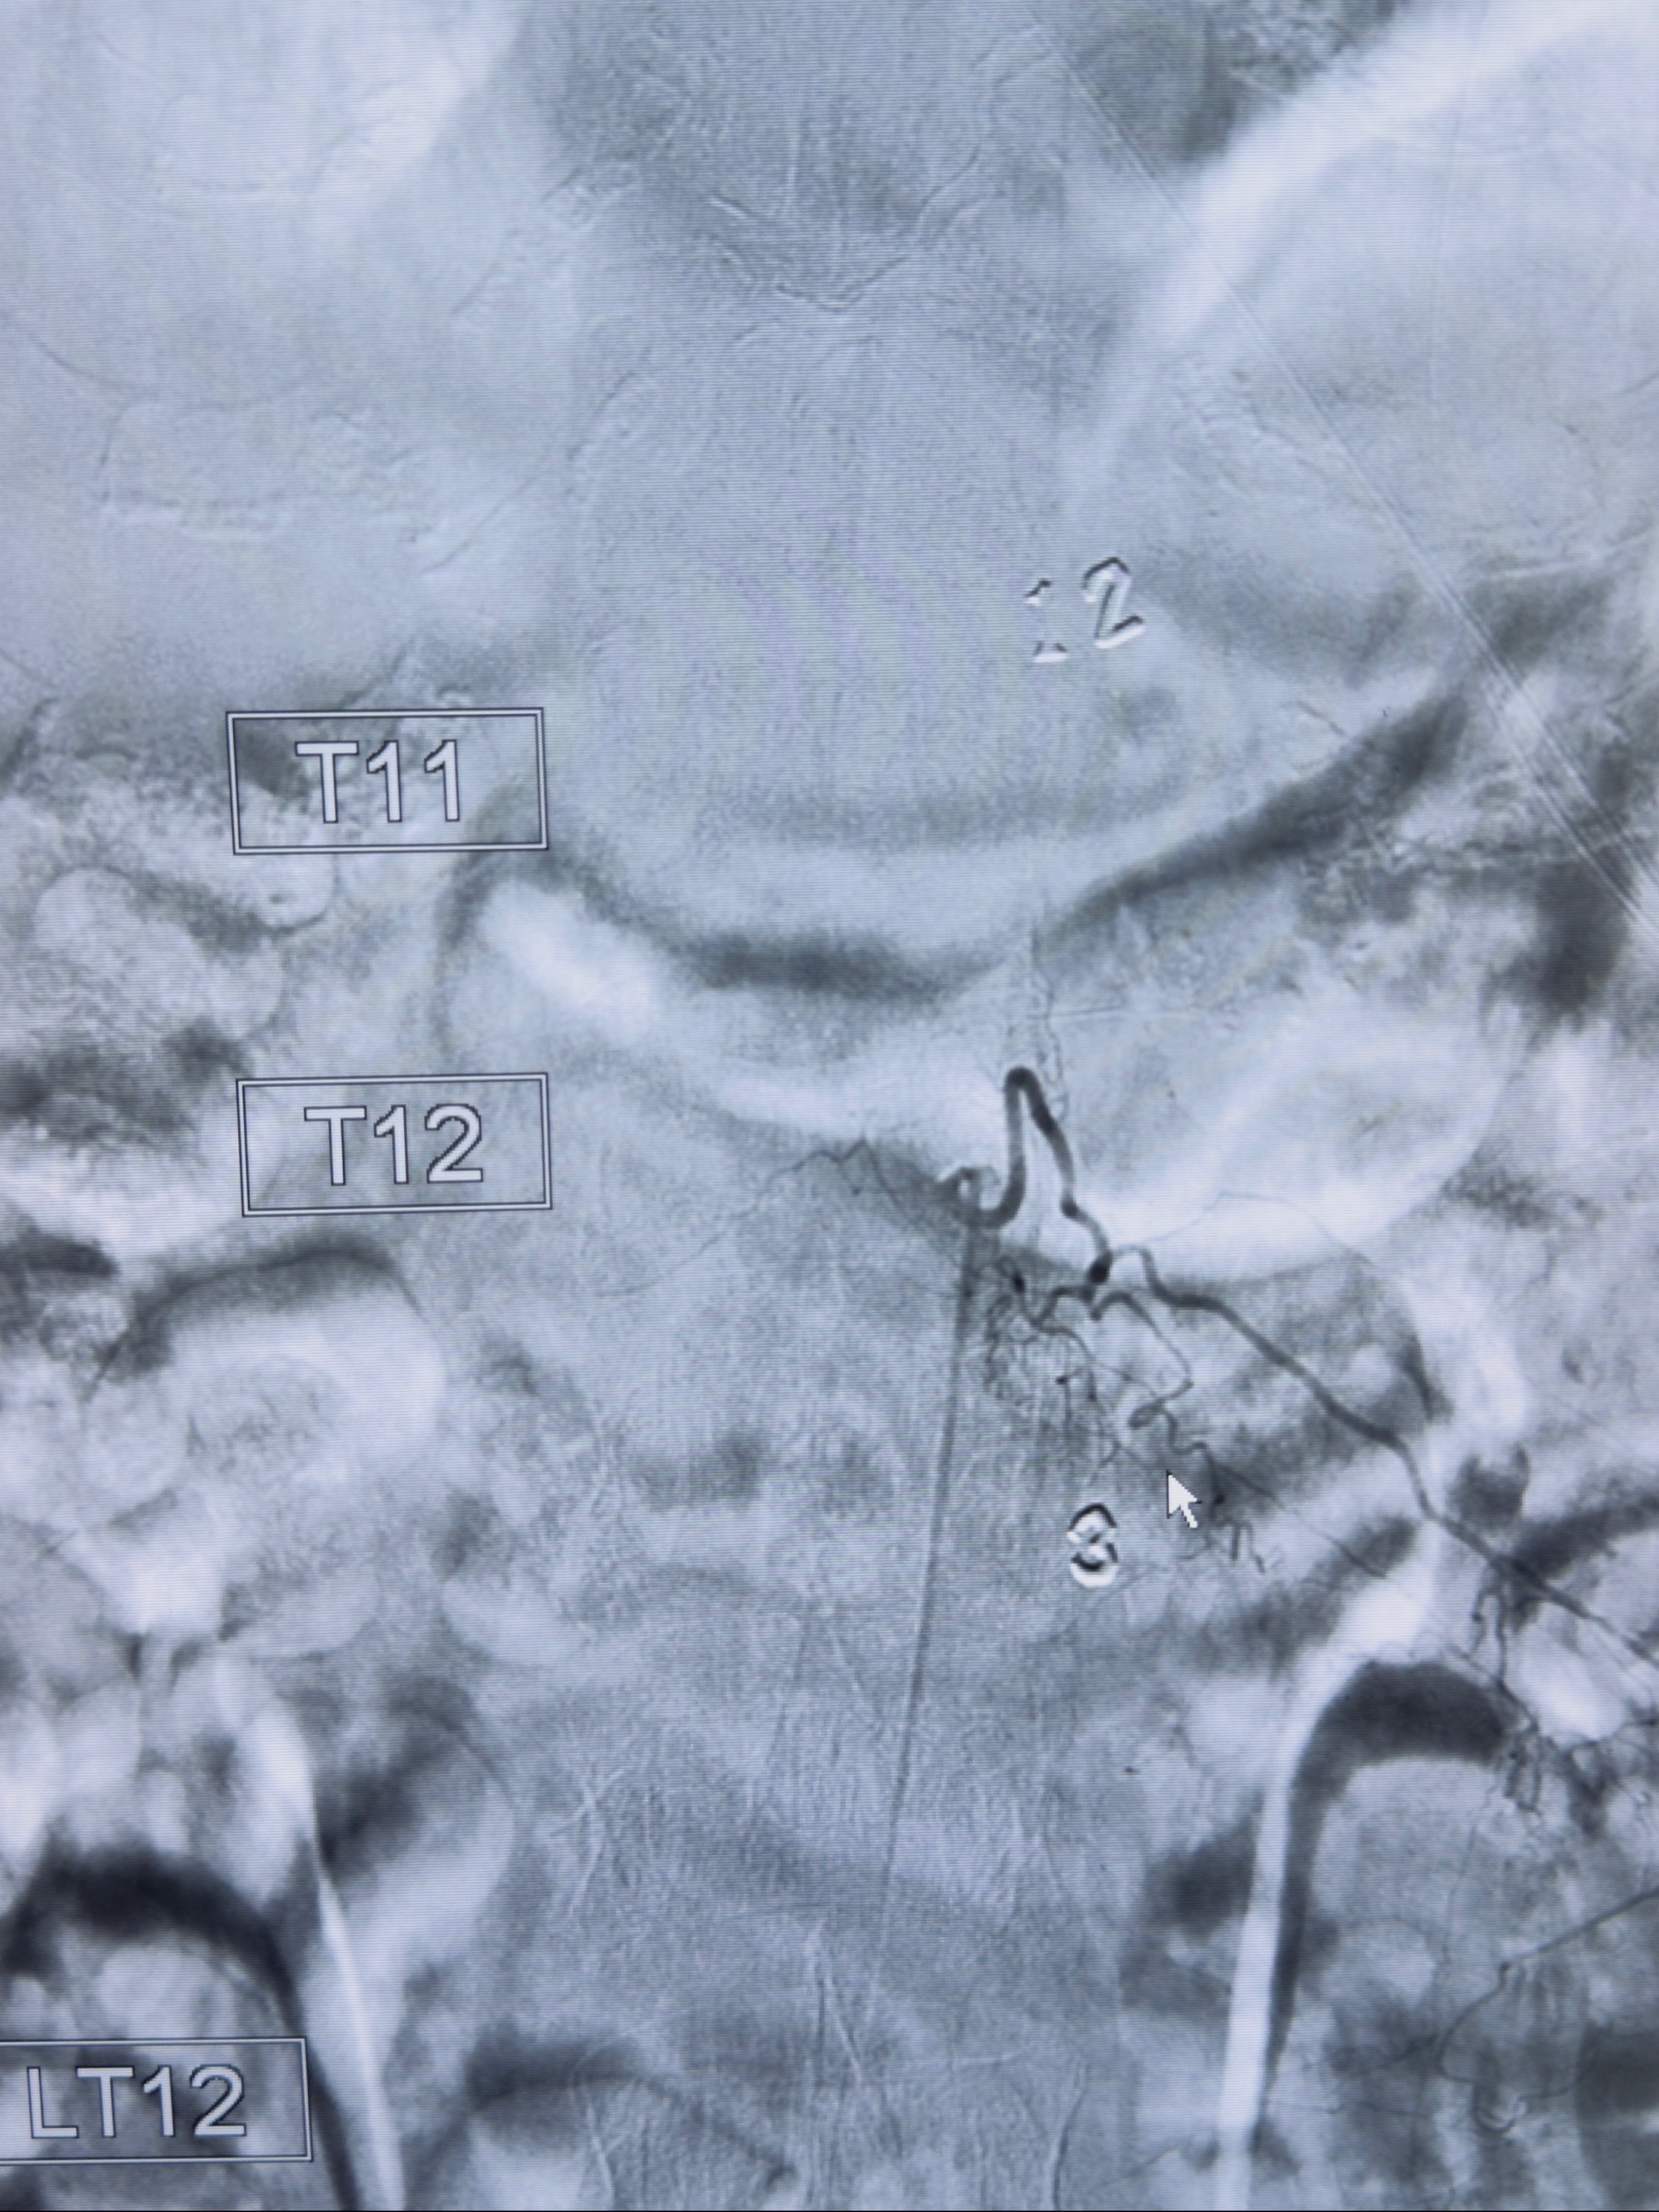

2023-10-13DSA:右侧L1水平硬脊膜动静脉瘘,供血动脉为右侧L1,附近动脉未见明确吻合供血,供血动脉处可见脊髓前动脉发出